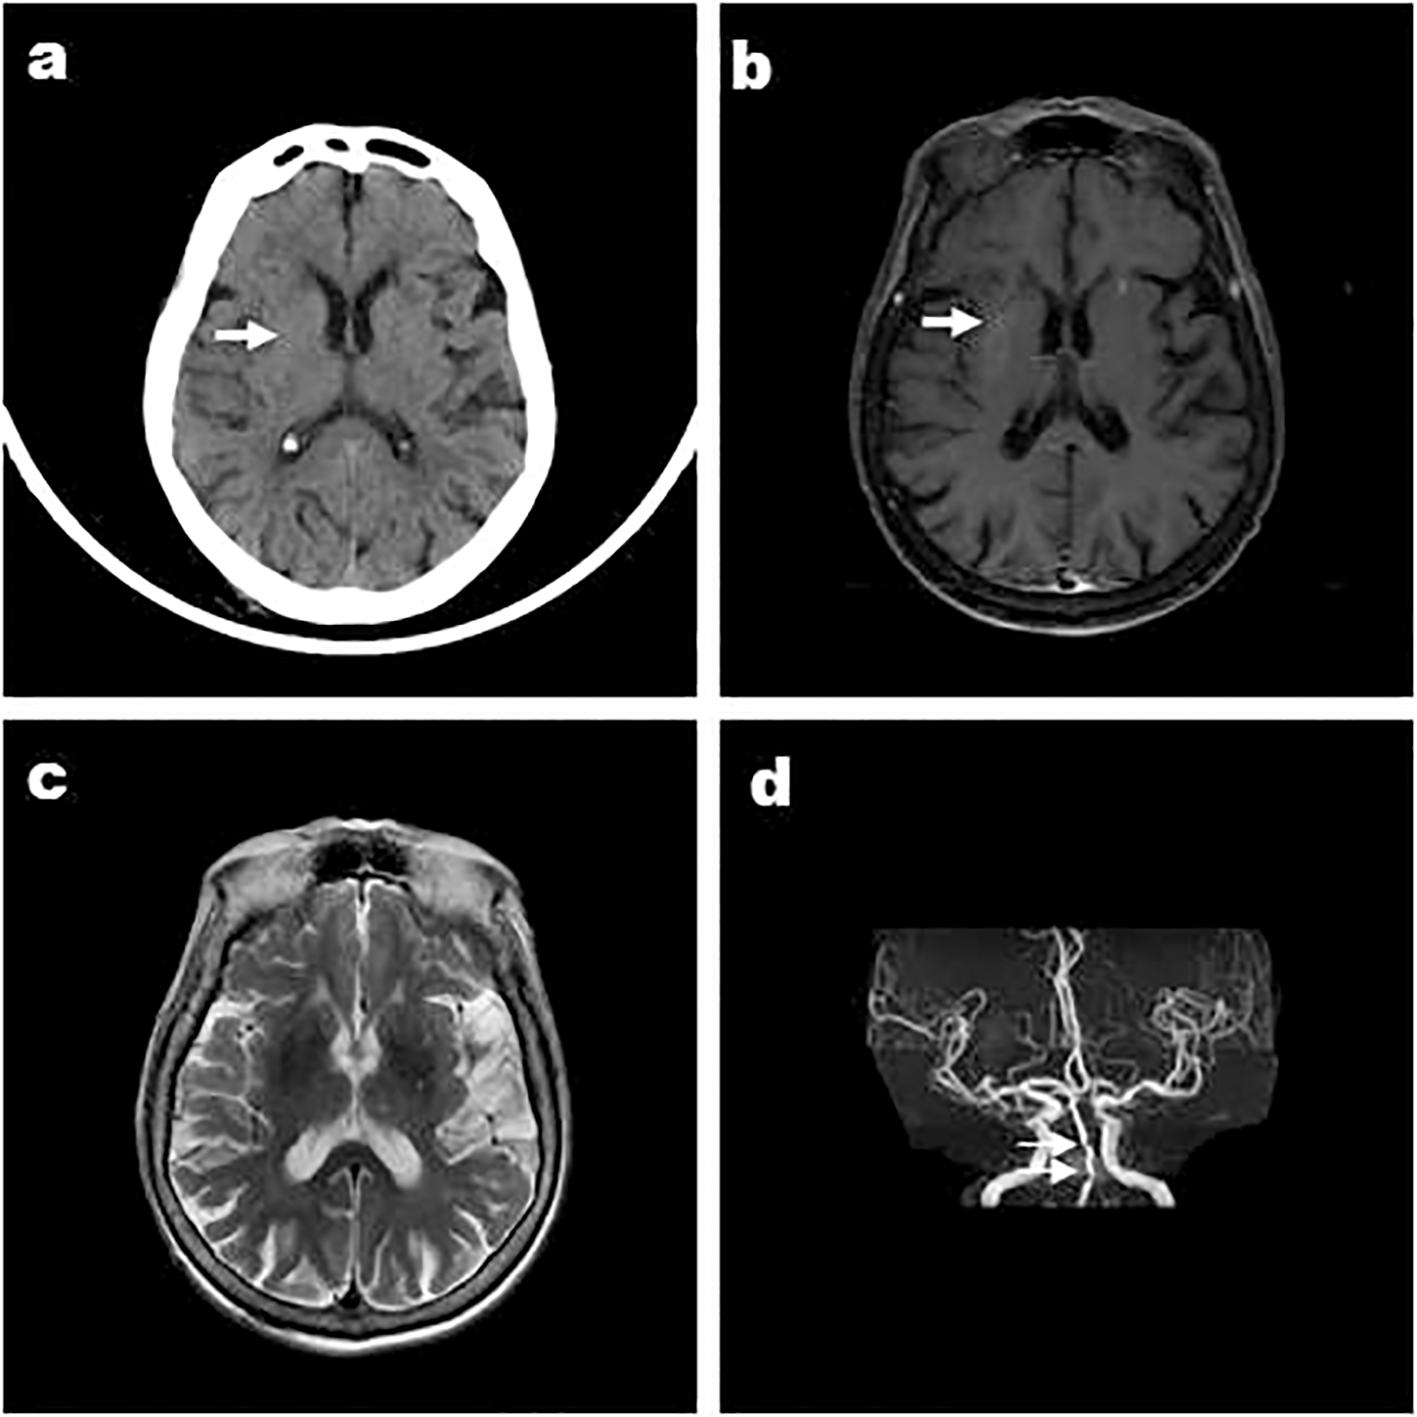

Figure 1

Case 3, a 66-year-old male, was admitted with “involuntary movement of the tongue and right limb for more than 1 month” and images showed bilateral striatum high density on CT (A), high signal on T1WI (B), iso-signal on T2WI (C), and MRA showed arterial stenosis (D). Arrows indicate bilateral striatum abnormal signal.

Except Case 5, all the cases underwent cranial CT and MRI examinations (Figures 2, 3). The characteristic images, hyperdensity on CT (Figures 1A, 2A, 3A) and high signal intensity on MRI T1-weighted sequences (Figures 1B, 2B, 3B) in the striatum, contralateral to the involuntary movement, were shown in Cases 1,2, 4, and 6. The signals on MRI T2-weighted sequences were variable (Figures 1C, 2C, 3C). In Case 3, hyperdensity in CT and hyperintensity in the T1-weighted image were shown on the bilateral striatum. In Case 5,the patient only had a cranial CT scan that showed a slight hyperdensity in the right basal ganglia. Normal signal in the right basal ganglia was shown in MRI diffusion weighted imaging (DWI) sequences in Case 6 (Figure 3E). A low signal in the right basal ganglia was shown in MRI susceptibility weighted imaging (SWI) sequences in Case 6 (Figure 3F).